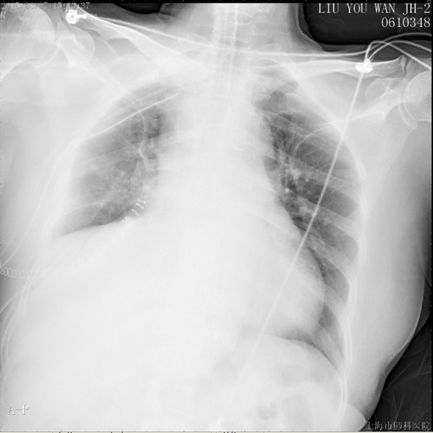

现病史:患者入院前体检发现右下肺占位28天,院外右下肺穿刺活检提示孤立性纤维性肿瘤,转入本院全麻下行心包内右肺中下叶切除和右胸腔肿块切除术,手术时间2.5h,术中失血100ml,无输血,术后病理显示梭形细胞肉瘤,倾向恶性孤立性纤维瘤,术后安返胸外科ICU,术后第一日胸引量350ml,无殊转回普通病房。次日清晨患者下床如厕后突发胸闷气促,脸色苍白,四肢湿冷,无晕厥。面罩吸氧后仍诉胸闷气促无法缓解。心电监护:SPO2 70%,HR 100-120bpm,BP 110/80mmHg。实验室检查:血气分析:pH 7.16↓, PaCO2 56.5mmHg, PaO2 43mmHg↓, SpO2 62.2%↓。

初步治疗:吸氧;经鼻气管插管,机械通气;低分子肝素6000IU皮下注射;患者神志清,自诉症状未缓解,术后第二日予以转入ICU。转入ICU后予机械通气,Vt 480ml,FiO2 100%,HR 128bpm,SPO2和血压进行性下降,需血管活*药性**维持。

此时患者由中高危逐渐转为高危,则予以个体化剂量溶栓治疗:阿替普酶(爱通立)10mg 2min静推,20mg 2h静脉泵入。溶栓2小时后,患者血氧饱和度明显上升,生命体征趋于平稳。后续抗凝维持方案:克赛6000 IU 皮下注射 Q12H。